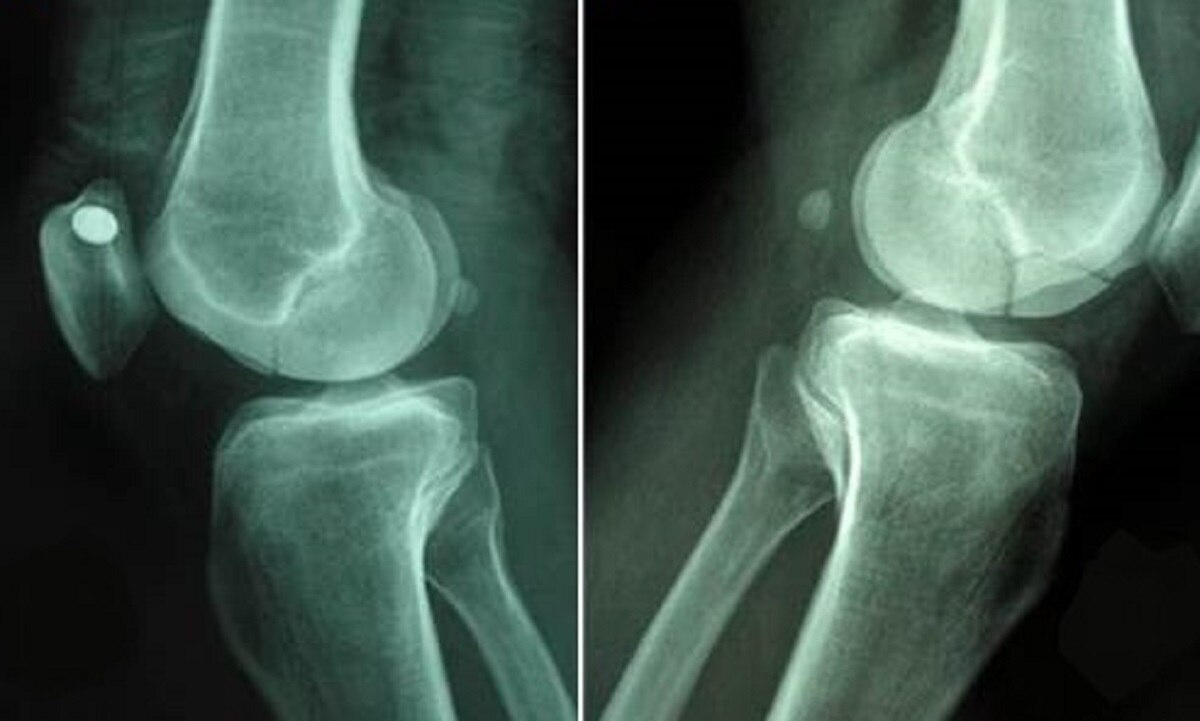

इकोनॉमिक टाइम्स की एक रिपोर्ट के मुताबिक एवैस्कुलर नेक्रोसिस के मुंबई में तीन मामले सामने आए हैं, जिन्हें साइंटिफिकली रूप से दर्ज कर लिया गया है. डॉक्टर्स इस बात को लेकर भी चिंतित हैं कि अगले कुछ दिनों में एवैस्कुलर नेक्रोसिस के मामले बढ़ सकते हैं. एवैस्कुलर नेक्रोसिस और एवैस्कुलर नेक्रोसिस के बीच स्टेरॉयड को एक बड़ा फैक्टर माना जा रहा है. यानी बीमारी से उबरने के लिए प्रयोग में लाए जा रहे स्टेरॉयड इसके लिए जिम्मेदार हो सकते हैं.

रिपोर्ट्स के मुताबिक, हिंदुजा अस्पताल में एवैस्कुलर नेक्रोसिस से जूझ रहे 40 साल से कम उम्र के तीन मरीजों का इलाज किया गया है. ये मरीज कोरोना से रिकवर होने के दो महीने बाद एवैस्कुलर नेक्रोसिस से ग्रसित पाए गए हैं. हिंदुजा अस्पताल के मेडिकल डायरेक्टर संजय अग्रवाल ने बताया कि इन मरीजों को फीमर बोन यानी जांघ की हड्डी में दर्द की शिकायत थी.

मेडिकल जर्नल बीएमजे केस स्टडीज में इस बीमारी पर 'एवैस्कुलर नेक्रोसिस ए पार्ट ऑफ लॉन्ग कोविड-19' के नाम से शनिवार को एक स्टडी भी प्रकाशित हुई है. इसके अलावा कई और डॉक्टर्स ने भी कोविड से रिकवरी के बाद एवैस्कुलर नेक्रोसिस के एक या दो मामले देखने की बात कबूल की है.

स्टडी में बताया गया है कि कोरोना इंफेक्शन से मरीजों को बचाने के लिए कॉर्टिकोस्टेरॉइड्स प्रीडनीसोलोन का बड़े पैमाने पर इस्तेमाल किया गया है, जिसके चलते एवैस्कुलर नेक्रोसिस मामलों में तेजी आई है.

ये स्टडी दो तरह के ट्रेंड को अंडरलाइन करती है. रिपोर्ट में दावा किया गया है कि कोरोना से रिकवरी के दौरान ऐसे मरीजों को कॉर्टिकोस्टेरॉइड्स प्रीडनीसोलोन के 758mg के डोज दिए गए थे. जबकि एवैस्कुलर नेक्रोसिस जैसी कंडीशन 2,000mg से ज्यादा डोज से ट्रिगर हो सकती है.

दूसरा, स्टेरॉयड के इस्तेमाल के बाद एवैस्कुलर नेक्रोसिस को विकसित होने में आमतौर पर छह महीने से एक साल तक का वक्त लग सकता है. लेकिन इन मरीजों में ये दिक्कत डाइग्नोज के 58 दिन बाद ही विकसित हो गई.

एवैस्कुलर नेक्रोसिस के कारण- एवैस्कुलर नेक्रोसिस स्टेरॉयड के अत्यधिक इस्तेमाल के अलावा बड़ी इंजरी, एल्कोहल के ज्यादा सेवन, ब्लड डिसॉर्डर, रेडिएशन ट्रीटमेंट, कीमोथैरेपी, पैंक्रियाटाइटिस, डीकम्प्रेशन डिसीज, ऑटोइम्यून डिसीज और एचआईवी के वजह से भी हो सकता है.